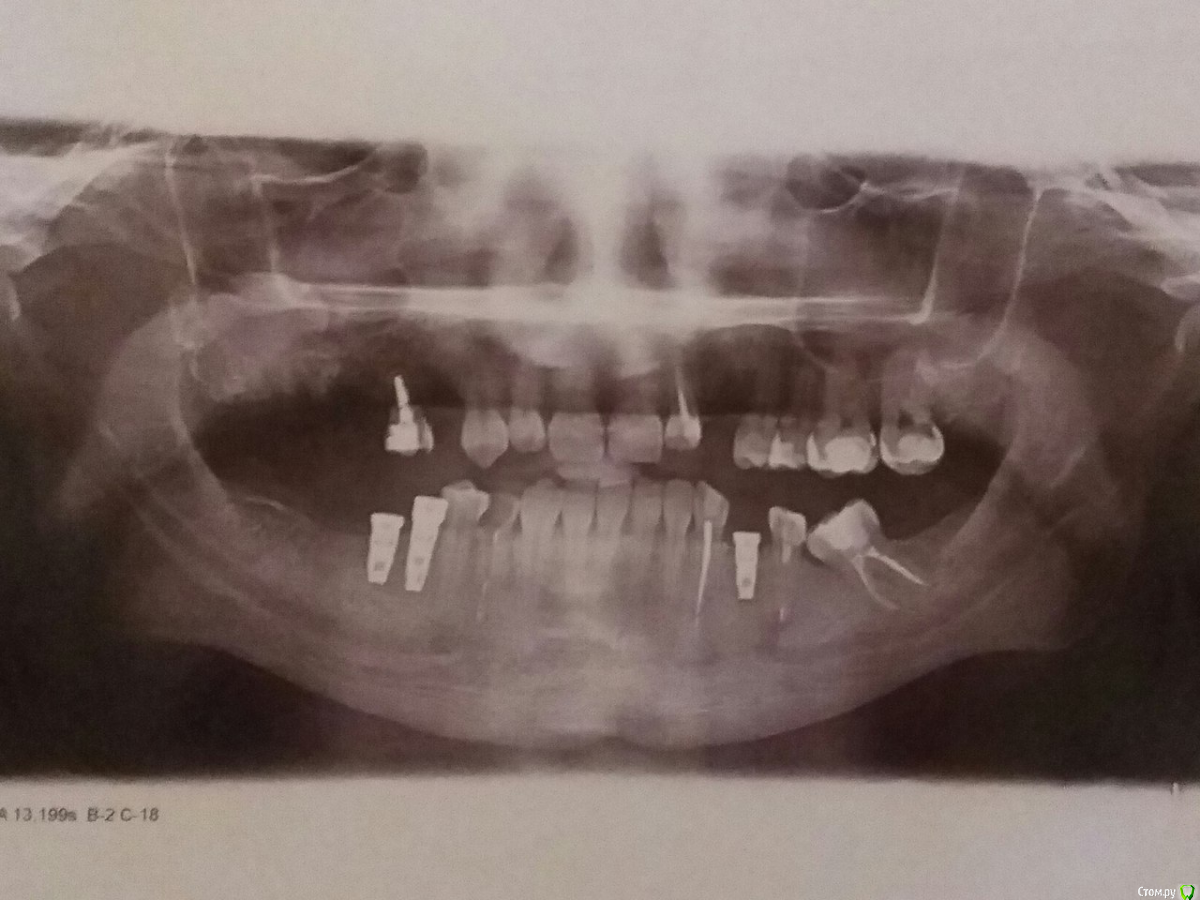

avetome Опубликовано 3 ноября, 2015 Автор Поделиться Опубликовано 3 ноября, 2015 (изменено) Добрый день. В общем, все очень плохо. Два шатающихся импланта врач просто выкрутил, как болт из стены. Сказал прийти к нему на следующий день. Я пришел на следующий день (т.е., 03.11), врач осмотрел лунки, сказал, что все хорошо, что кость на месте, что воспаление спало и что через полтора месяца попробуем еще раз. И еще порадовался, что третий имплант стоит хорошо. На вопросы о причинах этого отторжения и шансах следующего отвечал о-о-очень уклончиво. А сразу после приема врача я дошел до дома и сел перекусить. И в процессе приема пищи (ел я шоколадку, довольно мягкую), обнаружил, что и третий имплант начал шататься. Без объявления войны, без воспаления, без боли, за час до этого врач его осматривал, пробовал шатать и стучать по нему металлической штукой (которая с маленьким зеркалом на конце), и сказал, что с ним все было хорошо. И на тебе. Я добежал бегом до врача, благо он был еще на месте. И он так же вывернул мне и его, ничего толком не объяснив. В общем, мне очень интересно, что мне делать дальше. Врач говорит, что нужно пробовать ставить повторно, что он пропишет какие-то таблетки перед установкой, мол, пропью их и все будет хорошо. Но мне немного страшно пробовать еще раз не разобравшись, что было с этими имплантами. Может быть, нужно пройти обследования какие-нибудь (за месяц до имплантации проходил общий анализ крови и анализ на сахар, оба были хорошими, терапевт сказал, что беспокоиться не о чем). Может, нужно сменить тип импланта. Буду благодарен за любые советы о том, что нужно сделать, что бы повторная имплантация была удачной. Насчет кости. Кость я не наращивал, своей хватило. Когда делал КТ, врач-рентгенолог говорил, что кости у меня более чем достаточно. Так же зубной врач терапевт сказала, что у меня дисплазия эмали. Ну, вдруг это важно для этого случая. Насчет снимков: прямо сейчас в наличии только снимок сразу после имплантации. Есть еще КТ, которое делал перед имплантацией, но прямо сейчас я не могу сделать с него скрины, выложу завтра, если будет нужно. Так же могу сделать новый круговой снимок и выложить его, если скажете, что нужно. По графику лечения мне предстоит установка еще 4 имплантов в верхнюю челюсть в феврале (последнее удаление оттуда было в сентябре). Врач говорит, что отторжение имплантов в нижней челюсти на график никак не влияют, и стоит делать как задумали. А что вы думаете? Изменено 3 ноября, 2015 пользователем avetome Ссылка на комментарий